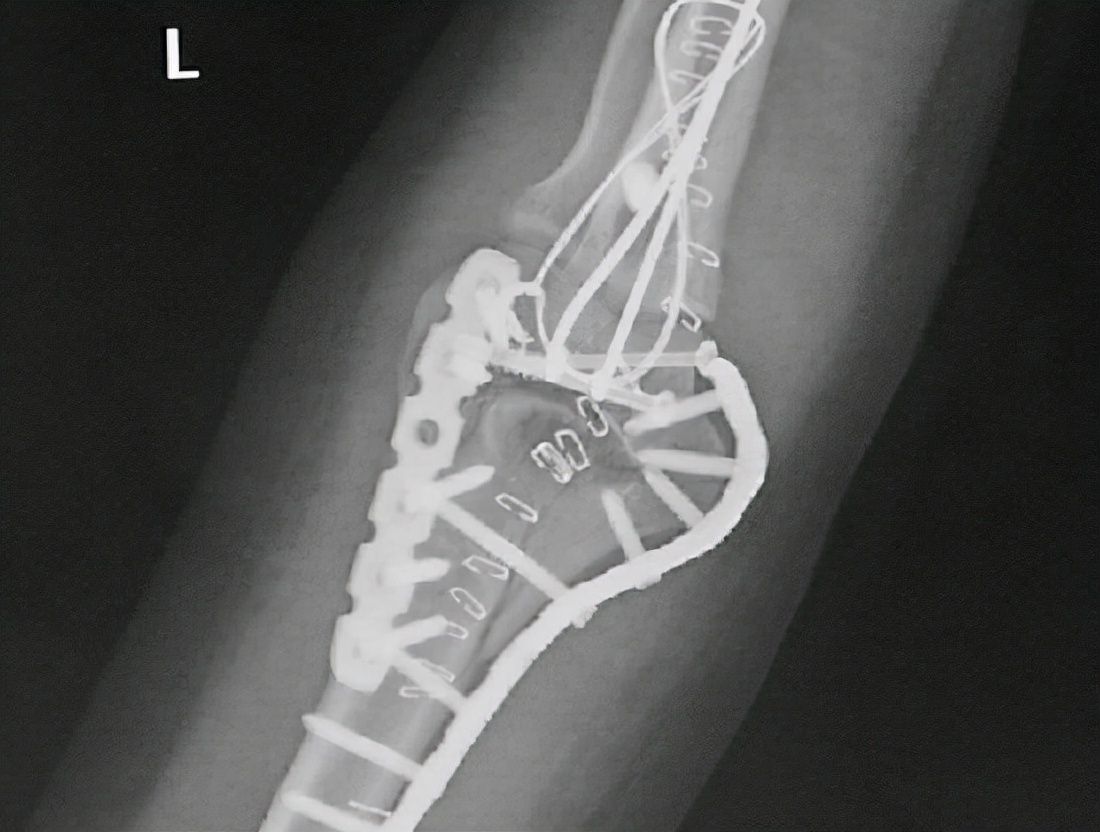

肘关节骨折后手术治疗的适应证 肘关节骨折后,如果符合如下任何一项适应证,通常都要实施切开复位固定的外科手术。1、骨折后断裂的骨块移位严重,且难以实施手法复位和制动的(错位显著的不稳定型骨折)。2、有软组织嵌入断端使骨骼愈合困难的;或者合并重要神经和血管损伤的。3、体型肥胖、脂肪肥厚者,难以进行手法复位并实施有效固定的。4、粉碎型的、断裂的骨块受到较大剪力,很难实施外固定的。5、患者不能配合,难以实施手法复位和持续制动的(例如:严重帕金森患者)。6、青壮年未能愈合的的陈旧性骨折。7、保守治疗失败的。8、发生骨筋膜室综合征的。

肘关节骨折后保守治疗的适应证 保守治疗的主要方法就是手法复位,然后用石膏、克氏针等方式在合适的体位下实施制动和固定,以确保骨折部位得到最佳固定并逐步愈合。保守治疗的优点是不会增加创口,但可能需要更长时间的制动,且不能保证精确的断端对线。肘关节骨折后,如果断裂的骨块无明显错位、无重要血管神经损伤、无软组织嵌入者,可实施保守治疗。另外,如果存在年龄大、骨质差、全身健康情况差、手术预后不佳、肘关节外部皮肤有感染等问题,应优先选择保守治疗。